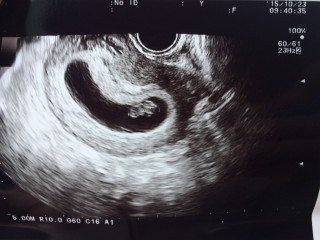

頭と胴体がはっきりしてきました。四週間前は4ミリのただの丸しか見えなかったのに、よくここまで大きくなるもんだと感心しかできません。 一週間で倍の大きさになったのも驚きです。頑張って大きくなってくれてるので、私も食生活に気をつけたいと思います。赤ちゃんの大きさは16.7mmです。